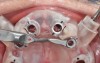

For dental implant-based treatment, the planning phase begins with collection of basic data sets; this is digital touchpoint 1. It includes: (1) a cone-beam CT (CBCT) to view edentulous areas or failing tooth structure, bone, and anatomic landmarks under the soft tissue (Figure 2 through Figure 4); and (2) an intraoral optical scan (IOS) or a scanned model or impression to record the soft tissue and tooth anatomy (Figure 5). The superimposition of the digital imaging and communications in medicine (DICOM) files from the CBCT and the standard tessellation language (STL) files from the IOS allows visualization of how bone, dental structures, and soft tissues relate. Both digital data points are key to implant selection and determining the surrounding bone-grafting needs. An initial treatment plan includes determining the desired implant manufacturer/implant design, size, and positions; these decisions remain the responsibility of the clinician (restoring and surgical team members) and not the technician or planning team.

From the data and collaboration in steps 1 through 3, surgical guides can be fabricated for static surgery, and when indicated, prosthetic components, such as custom healing abutments, provisional crowns, or fixed partial dentures, can be produced for delivery at the time of surgery to guide soft-tissue healing. The static approach, better known as computer-guided surgery, refers to the use of tissue-tooth or soft- and hard-tissue-supported surgical templates. In essence, the virtual implant position planned from the CBCT, IOS, and face-in data sets is reproduced. The guide is produced with master cylinders (portals) through which the osteotomy preparation drills are introduced, and in full-guidance cases, the delivery of the implant is carried out (Figure 14 and Figure 15). Dynamic guided surgery or computer "navigation" traces the virtual implant position directly from CBCT data and employs motion tracking or real-time tracking technology to prepare the implant osteotomy. This makes it possible to determine the actual position of the surgical drill on the reconstructed 3D image provided by the CBCT. The surgeon is guided to the position that was planned preoperatively while he or she performs the surgical procedure. Examples of dynamic navigation systems are Navident (ClaroNav, claronav.com), X-Guide Dynamic 3D Navigation (X-Nav, x-navtech.com), Image Guided Implant (IGI) Dentistry System (Image Navigation, image-navigation.com), Inliant® (Navigate Surgical, navigatesurgical.com), and YOMI®, a robotic haptic guidance system (Neocis, neocis.com).

Guided surgery, whether it be static or dynamic navigation, improves accuracy in comparison to free-handed implant placement procedures.8,9 Static surgery may involve the use of laboratory-processed stereolithographic guides to both prepare the osteotomies and deliver implants.10 Other than in regions with limited access, these accurate guidance templates can be considered for use in any scenario. Dynamic navigation offers advantages in these types of situations. Although linear and angular deviations between planned and executed implant positions are possible and probable, operator experience and use of appropriate hardware can minimize these deviations.11,12